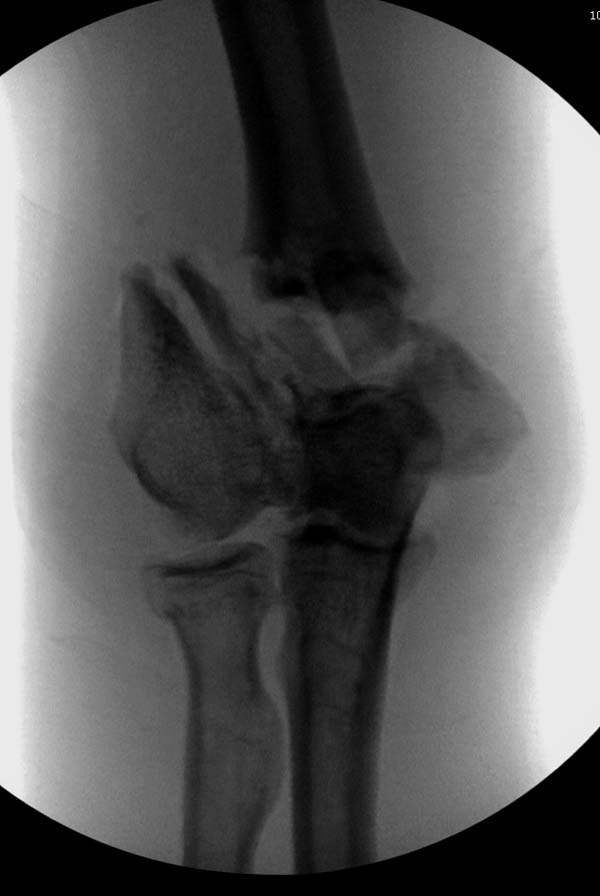

Из представленнего материала видно, что между снимками нет разницы.

Отсутствует репозиция не только медиального, а также латерального

мыщелка. На боковом снимке мыщелок расположен спереди, а прямом головка

луча упирается в край мыщелка, что означает ротацию. Отсутствует

компрессия между мыщелками, а один шуруп не смог удержать медиальную

сторону, которая при первом же движении рассыпалось.